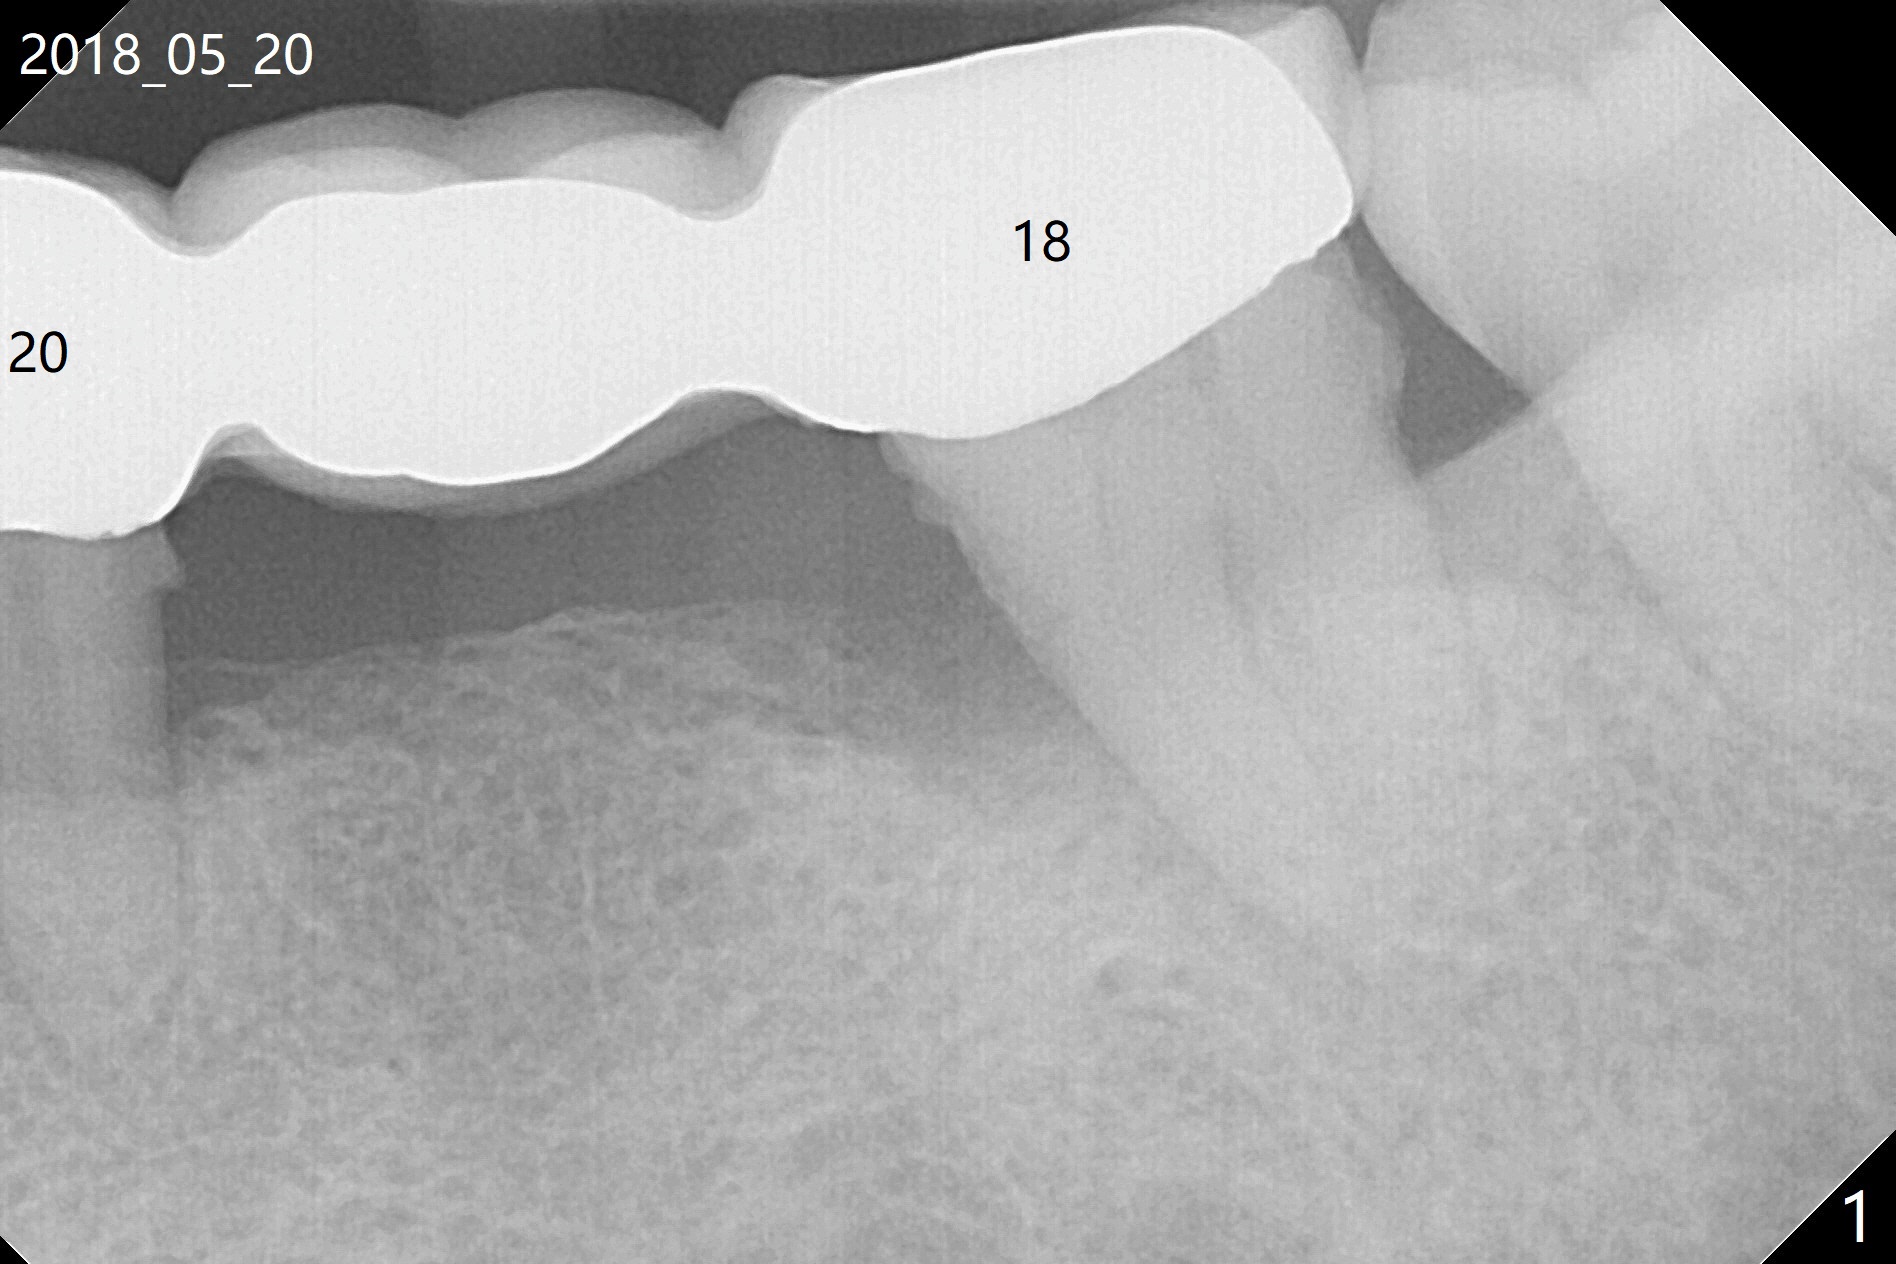

A 46-year-old woman had severe periodontal abscess lingual to #18-20 FPD a year ago (Fig.1,2 *). After SRP and Arestin placement #18 ML, the FPD was sectioned (Fig.2 >) to determine which abutment is to be extracted for implant. Since the sectioning, the patient has been unable to masticate on the left side (Fig.3). With removal of the FPD, CT is taken for surgical guide. Are the abutments salvageable (Fig.4,6)?